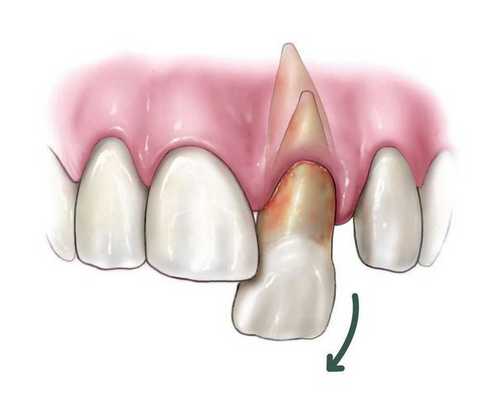

Отведите в сторону мыщелки и вправьте челюсть:

Поместите большие пальцы на наружный косой отросток с обеих сторон нижней челюсти, по бокам от третьих моляров. В качестве альтернативы оберните пальцы слоями марли и поместите их как можно более сзади на окклюзионную поверхность нижних моляров с обеих сторон (это увеличивает риск укуса во время вправления).

Сожмите другие пальцы вокруг и под нижней челюстью, указательными пальцами позади ветви. Пальцы должны контактировать с костью нижней челюсти, а не с мягкими тканями под языком.

Во-первых, прикладывают постоянное и непрерывное, направленное книзу, усилие на заднюю часть челюсти, используя свои большие пальцы, чтобы сдвинуть мыщелки ниже. Это постоянная, устойчивая сила, а не резкое, дёргающее, толкающее усилие.

Одновременно на переднюю часть нижней челюсти прикладывают аналогичную силу, направленную вверх (т.е. качнуть подбородок вверх), что может улучшить вправление мыщелка.

Основная задача заключается в том, чтобы сначала оказать значительное давление вниз в задней части челюсти, затем медленно направлять всю нижнюю челюсть назад: «Вниз. затем назад». Часто нижняя челюсть щелкает в положение, когда мыщелки открывают суставной бугорок.